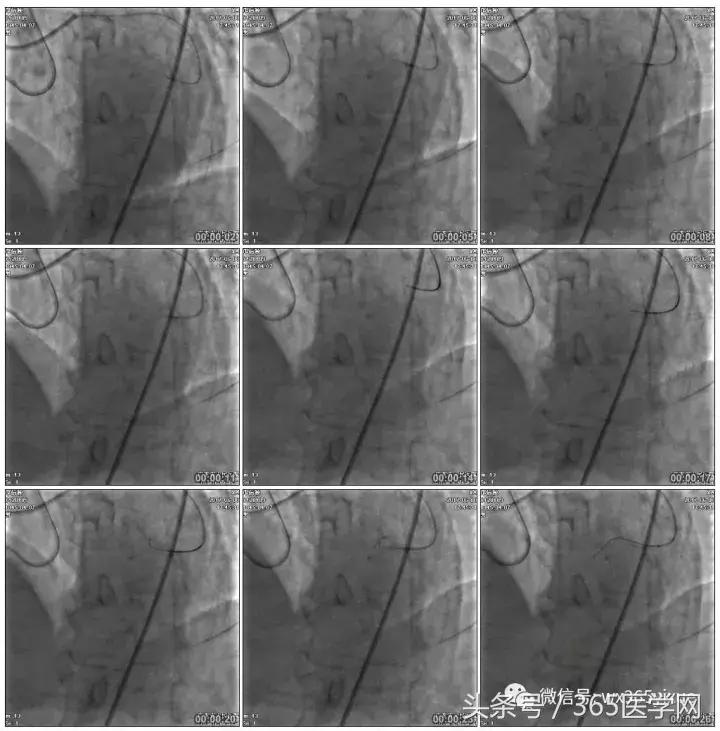

1.正向2.5*15mm球囊扩张,Reverse CART

2.Guidezilla延长导管辅助下,逆向导丝进入正向GC

1.更换RG3导丝

RCA闭塞段球囊扩张后IVUS

支架术后造影结果

支架术后IVUS